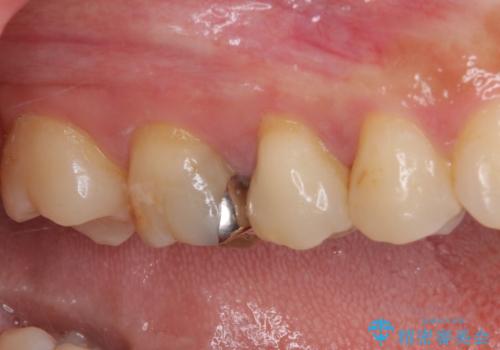

処置後に痛みを感じることはなく、冷たいものがしみることもなくなりました。

奥の大臼歯にもむし歯があったので、一緒に処置を行いました。